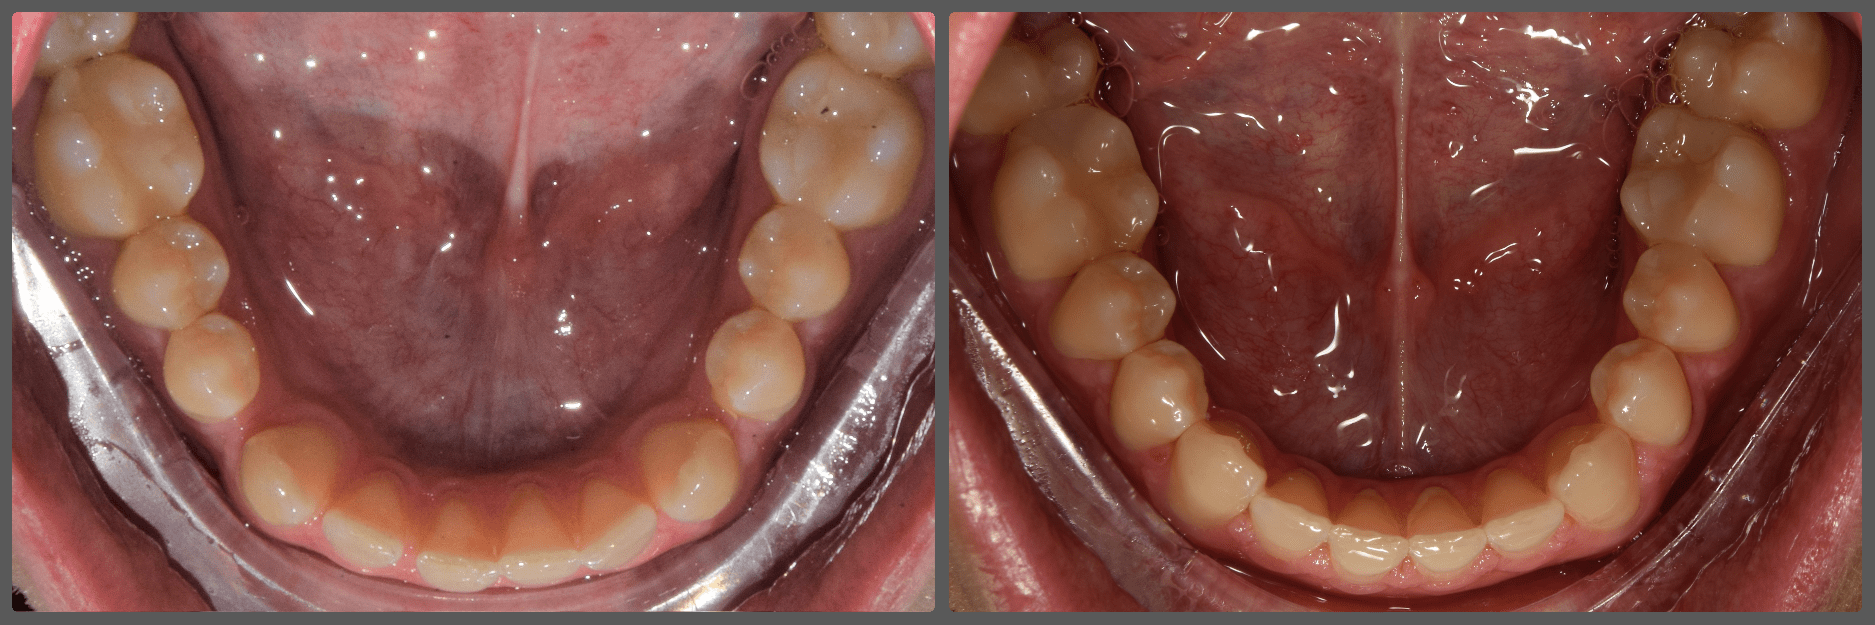

Balázs súlyos alsó torlódása miatt keresett fel magánrendelésemen. A diagnosztikus vizsgálatok során előbbin túl alsó-felső fogívszűkületet, valamint nyitott harapási hajlamot állapítottam meg. Kezelését Pitts21 alsó-felső rögzített fogszabályozó készülékkel kezdtük meg. A nyitott harapási hajlamot a hátsó fogakra helyezett harapásemelővel kontrolláltuk. A torlódott fogaknak tolórugóval és interproximális redukcióval teremtettünk helyet, és intermaxilláris gumihúzással tökéletesítettük a harapást. A fogszabályzó kezelés teljes időtartama alatt Balázs 110%-osan együttműködő volt, ezért 21 hónap alatt sikerült kiemelkedő végeredményt elérnünk.